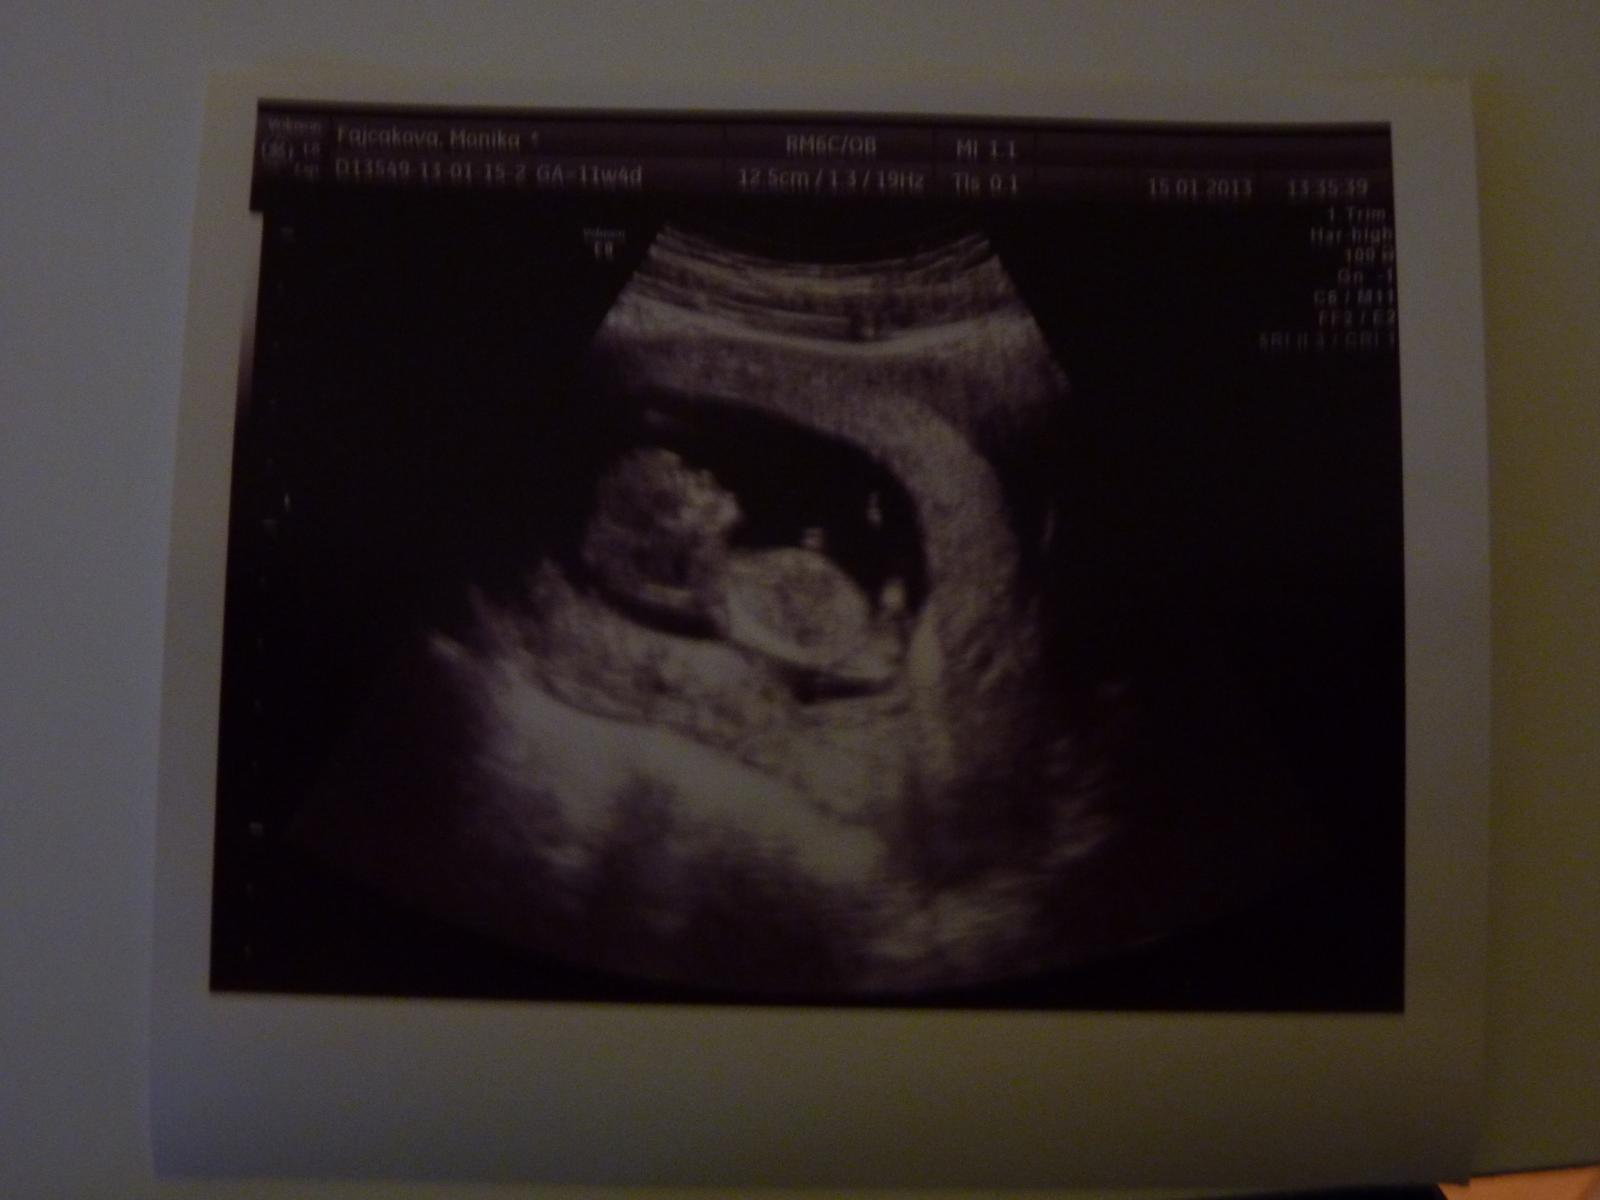

@lylkatomaskova Svagrina bola na zaciatku 12. tt a na foto krasne vidiet aj rucicky a nozicky, babo vyzera ako taky medvedik 🙂

@lylkatomaskova toto je fotka z 12.týždňa a určite sa oplatí 😉

@lylkatomaskova ahoj,urcite sa to oplati,ak ho pan doktor dobre odfoti 🙂 vidiet rucicky,nozicky,dokonca co mam videozaznam zo sona,vidiet detailne aj prstiky na nozicke...je to uzasne 🙂

ahojte, tak kontrola dopadla super, az na zvyseny krvny tlak, mam brat magne b6 2x denne a merat si doma tlak kazdy den. ak presiahne 140/90 musim ist ihned k dr. a naspat na pn potom ☹. inak na krv kvoli triple testom idem 18.2. a poradnu mam 26.2.. takze zajtra sa ide do prace a uz mozeme aj cvicit aj sexikovat ale s mierou 😀 ! prikladam foto, kde uz pekne vidno chrbticu a meral mi uz len hlavicku plodu - 2cm 🙂